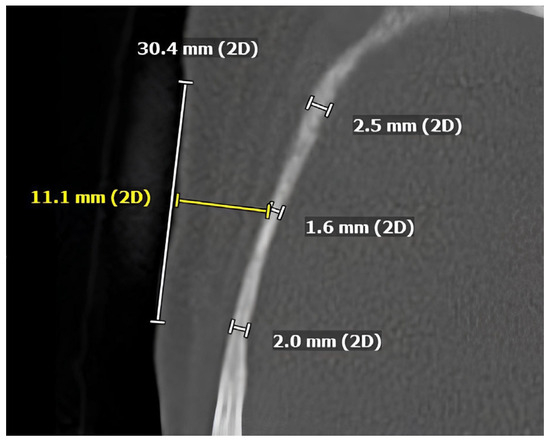

Horizontal Platelet-Rich Fibrin Membrane Block for Peri-Implant Soft Tissue Augmentation: An Experimental Animal Study with Clinical Illustration

Background/Objectives: Adequate peri-implant soft tissue thickness is essential for long-term peri-implant health and esthetics. Horizontal platelet-rich fibrin (H-PRF) has been proposed to support soft tissue regeneration; however, experimental and translational evidence for its application in peri-implant soft tissue augmentation remains limited. This study [...] Read more.

Background/Objectives: Adequate peri-implant soft tissue thickness is essential for long-term peri-implant health and esthetics. Horizontal platelet-rich fibrin (H-PRF) has been proposed to support soft tissue regeneration; however, experimental and translational evidence for its application in peri-implant soft tissue augmentation remains limited. This study aimed to evaluate a H-PRF membrane block approach primarily through an experimental animal model, with clinical cases presented to illustrate translational feasibility. Methods: A customized compression device was used to fabricate the H-PRF membrane block. The biological performance of the H-PRF membrane block was first evaluated in a rabbit model, with histologic assessment of peri-implant soft tissue thickness and integration at 8 weeks. Representative clinical cases requiring peri-implant mucosal thickening were subsequently treated with H-PRF membrane block on the buccal aspect of the alveolar bone beneath a supra-periosteal flap to demonstrate clinical applicability. Results: In the animal model, the H-PRF membrane block resulted in a significant increase in peri-implant soft tissue thickness by increasing the lamina propria compared with control sites demonstrated by histologic analysis. The clinical illustrations showed stable buccal soft tissue volume and contour with minimal patient morbidity. Conclusions: Within the limitations of this experimental study, the horizontal H-PRF membrane block technique demonstrated promising biological performance for peri-implant soft tissue augmentation in an animal model. The accompanying clinical illustrations support the translational feasibility of this approach. Clinical relevance: This experimental study provides biological and translational insight into a minimally invasive strategy for peri-implant soft tissue thickening and may inform future controlled clinical investigations. Full article